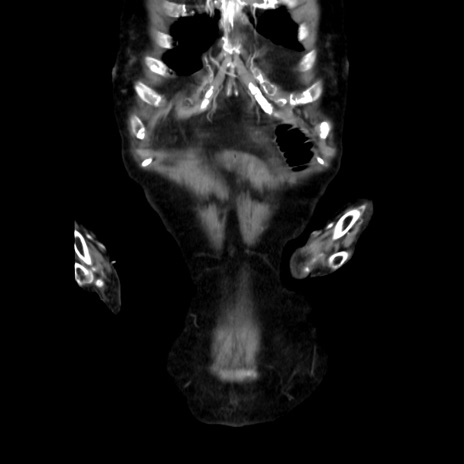

症例40(冠状断像)

冠状断像